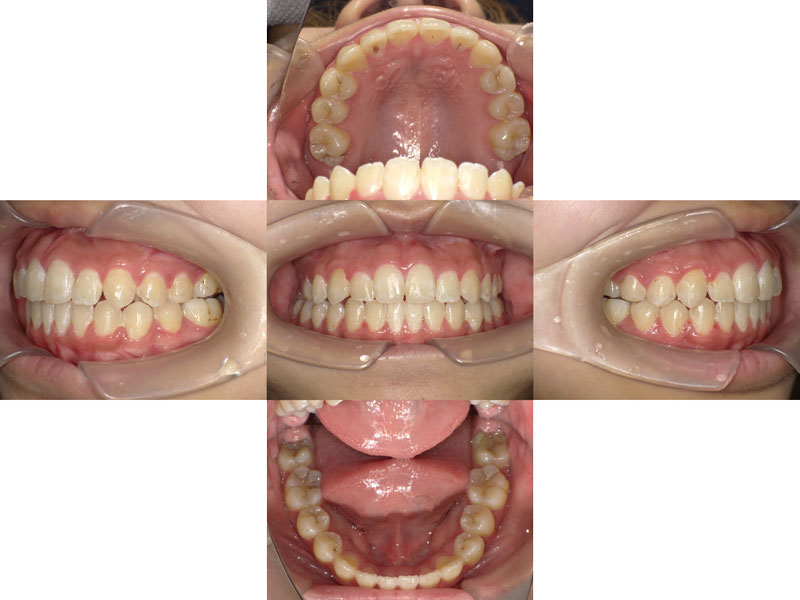

After

診断 ClassⅠ 叢生 開口 顎変位

治療内容 ・ワイヤーによる全顎矯正

・小臼歯非抜歯

治療のポイント 小臼歯非抜歯

小臼歯(特に第一小臼歯・犬歯の一つ奥の歯)は、機能的に正常な咬み合わせには絶対必要で抜歯してはいけないという方針で治療を行っています。

実際、小臼歯を抜かないでも、歯の傾斜と咬合平面の適正化により、歯が並ぶスペースが足りていることがほとんどです。

この患者様も、検査の結果、小臼歯を抜歯する必要はないという診断のもと、矯正治療を行い、良好な結果を得ることができました。